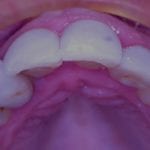

Anterior preps scanned along with the opposing and the initial bite

segmental imaging to building a master model

upper and lower models related to each other for design